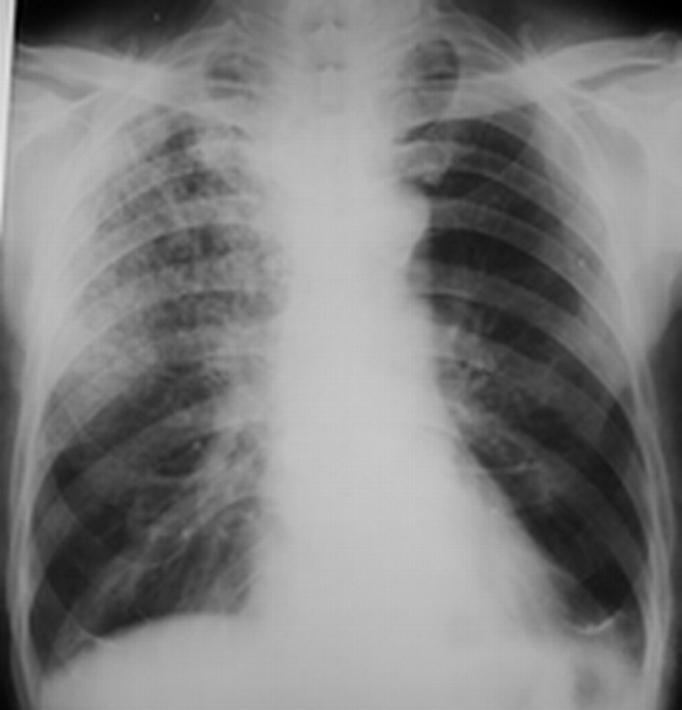

男,85岁。胸闷,咳嗽

右上肺见小片状,斑点状及粟粒状阴影,其密度不均,边缘模糊。

考虑右上肺结核。

右上肺继发型肺结核。

诊断依据,阴影多态性,分布在上叶,鉴别转移。

右上肺斑点状阴影,呈类似结节样,未见到明显的纤维索状及钙化影,肺门也无改变,从年龄来看,继发型肺tb应该会合并有纤维索状影及钙化影,所以我的意见:

1,支气管肺泡癌可能性大于右上肺继发型肺tb;

2;慢支并肺气肿。

建议:ct检查

考虑1、右上肺结核。2、阻塞性肺炎待排。

双肺多发小结节状阴影,密度较高,以右上肺为著,至于双肺尖有无无法判断,可以考虑血播(硬结/钙化),但尘肺不能除外,追问职业接触史,另外看看肺尖有无病灶对诊断有帮.

右上中肺野见斑点状及条索样密度增高影,部分边缘较清楚,右下及左肺透亮度增加,肺门影不大。右上纵隔影增宽,边缘较模糊。

考虑:右上中肺感染性病变(结核可能性大)。建议作进一步检查。